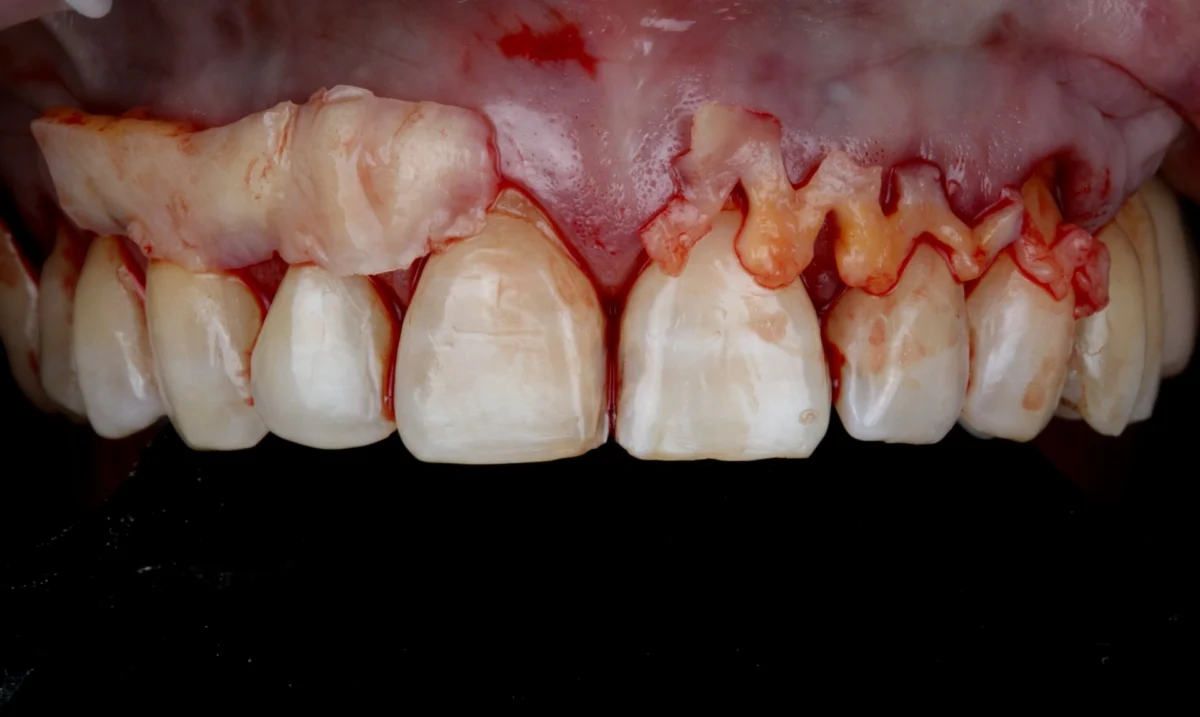

El injerto de encía es un procedimiento quirúrgico destinado a corregir la recesión gingival, es decir, cuando las encías se retraen y dejan expuesta la raíz del diente. Este tratamiento consiste en tomar tejido de una zona donante, generalmente del paladar, o utilizar materiales biocompatibles, para cubrir las áreas afectadas y proteger las raíces expuestas.

El injerto de encía no solo mejora la estética de la sonrisa, sino que también previene la sensibilidad dental y el riesgo de futuras complicaciones como caries radicular o pérdida de hueso. Además, refuerza la estructura de las encías, proporcionando una protección duradera.